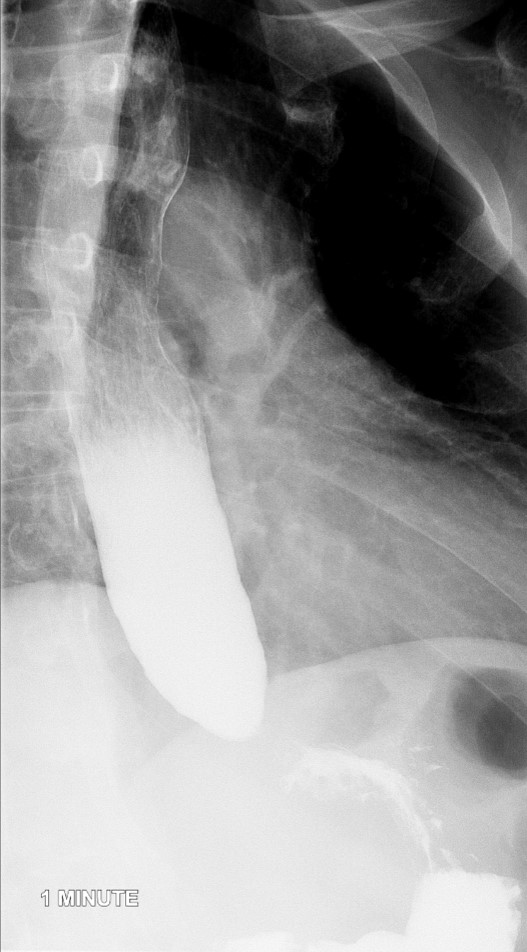

- Obtain spot radiographs of the distal esophagus at 1, 2, and 5 minutes after ingestion of the barium

(key image 1)

(key image 2)

(key image 3).

- Ensure the distance between the patient and the fluoroscope is kept constant between all 3 radiographs.

- If the barium contrast material completely clears the esophagus at 1 or 2 minutes, do not take the subsequent spot images.

- Images are obtained in the upright LPO projection.

- Films are obtained 1 minute, 2 minutes, and 5 minutes after contrast material administration.

- If contrast has emptied from the thoracic esophagus on the one minute image, the 2 minute and 5 minute images are not needed.